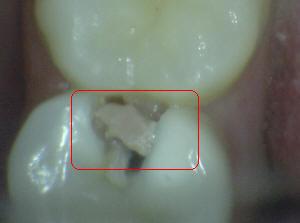

¿Determine los códigos pertinentes a cada imagen?

Click en el hipervínculo: Para comparar el resultado de su diagnóstico